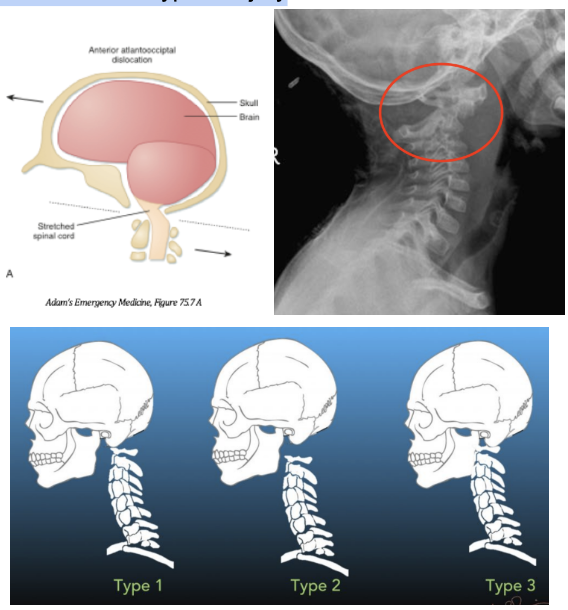

A - Atlanto-occipital dislocation (AOD)

1. Highly unstable injury that is also called “internal decapitation” as it results in complete dissociation of C1 from the occiput due to rupture of the transverse ligaments stabilizing the atlanto-occipital joint

2. Different presentations, but the most common is anterior dislocation (type 1), but can also occur superiorly (type 2), and posteriorly (type 3)

3. Highly fatal injury due to stretching of the brainstem causing respiratory arrest and death

4. More common in pediatric patients due to immature atlanto-occipital joint and certain high-risk populations (ie. Down’s syndrome, rheumatoid arthritis) due to increased laxity at the AO joint

5. This injury can easily be missed on imaging since the joints may reapproximate between the time of the incident and imaging. Physical exam findings like mandibular fx, chin lacerations, and injury to the posterior pharyngeal wall can clue you into the this type of injury